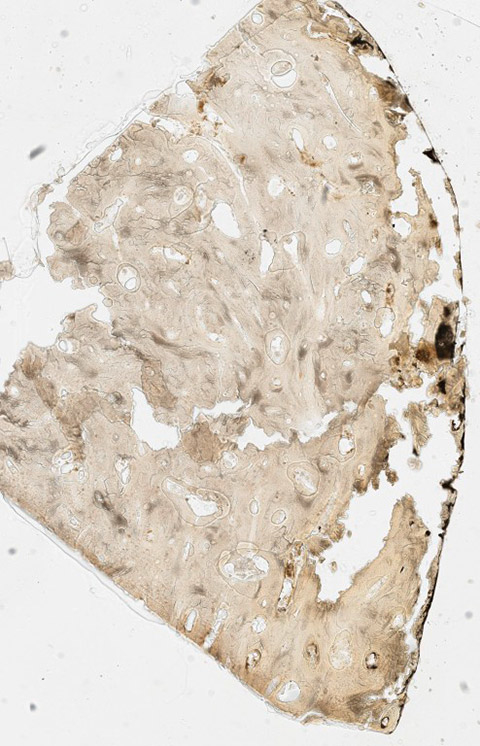

Figure 7

Hard-cut section 1.25x. Sample taken out of the lesion.

The remains are well preserved. Morphological examination of skull and pelvis clearly classify the individual as female. The age at death was between 30 and 50 years. There is an intensely calcified bone proliferation at the right side of the os frontalis (fig. 2). Plain X-ray and CT imaging show a large (5.3 x 3 x 8.7 cm) sclerotic lesion in the area of the right temple with a partly bulging appearance (fig. 4). Figure 5 shows representative slices of the admission CT. A differentiation between tabula interna, diploë and tabula externa is not possible in major parts of the lesion. The inner boundary of the lesion shows multiple smooth-edged irregularities. There is a diffuse thickening of the right skull vault (right 7 mm, left 4 mm). The left skull vault presents a mix of sclerotic areas and areas with normal appearance with a clear differentiation between tabula interna, diploë and tabula externa. CT imaging and plain X-ray show a wedge-shaped area in the centre of the lesion that is filled with material of lower X-ray density than the adjacent bone (figs 5 and 6). Histology shows mature organised lamellar bone tissue with ordered formation of trabeculae (figs 7–9). No pathological alterations were found in the postcranial bones.

Histomorphological analysis revealed mature, structured lamellar bone without indication of an associated immature or fibrous component. The bone lesion is dense and without evidence of lytic areas. Although viable cellular components, which could have shown signs of nuclear atypia, could not be demonstrated, the mature architecture of the remnant bone structures do not raise the suspicion of malignancy.